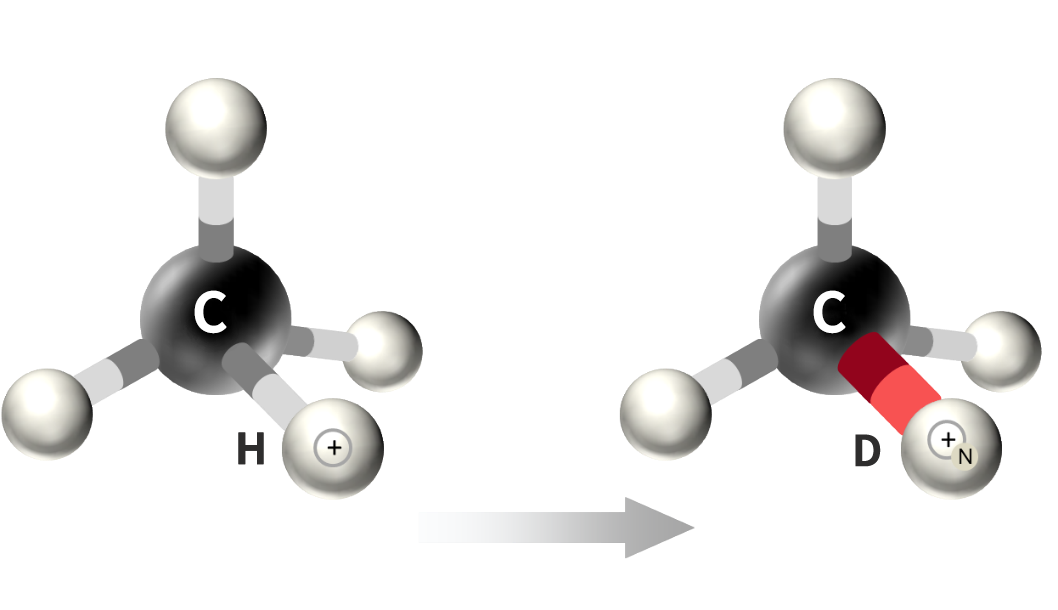

Deuterated Drug R&D Platform

Competitive Advantages of Hinova Deuteration Technology Platform